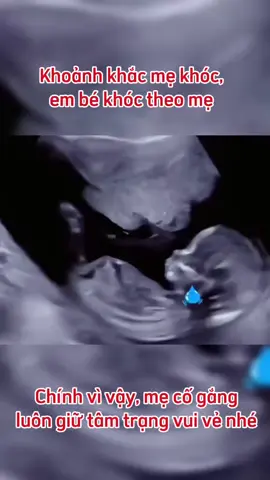

Cố lên mẹ nhéé , chỉ khi mẹ vui thì con mới vui #xuhuongtiktok #mebauthongthai #embedangyeu